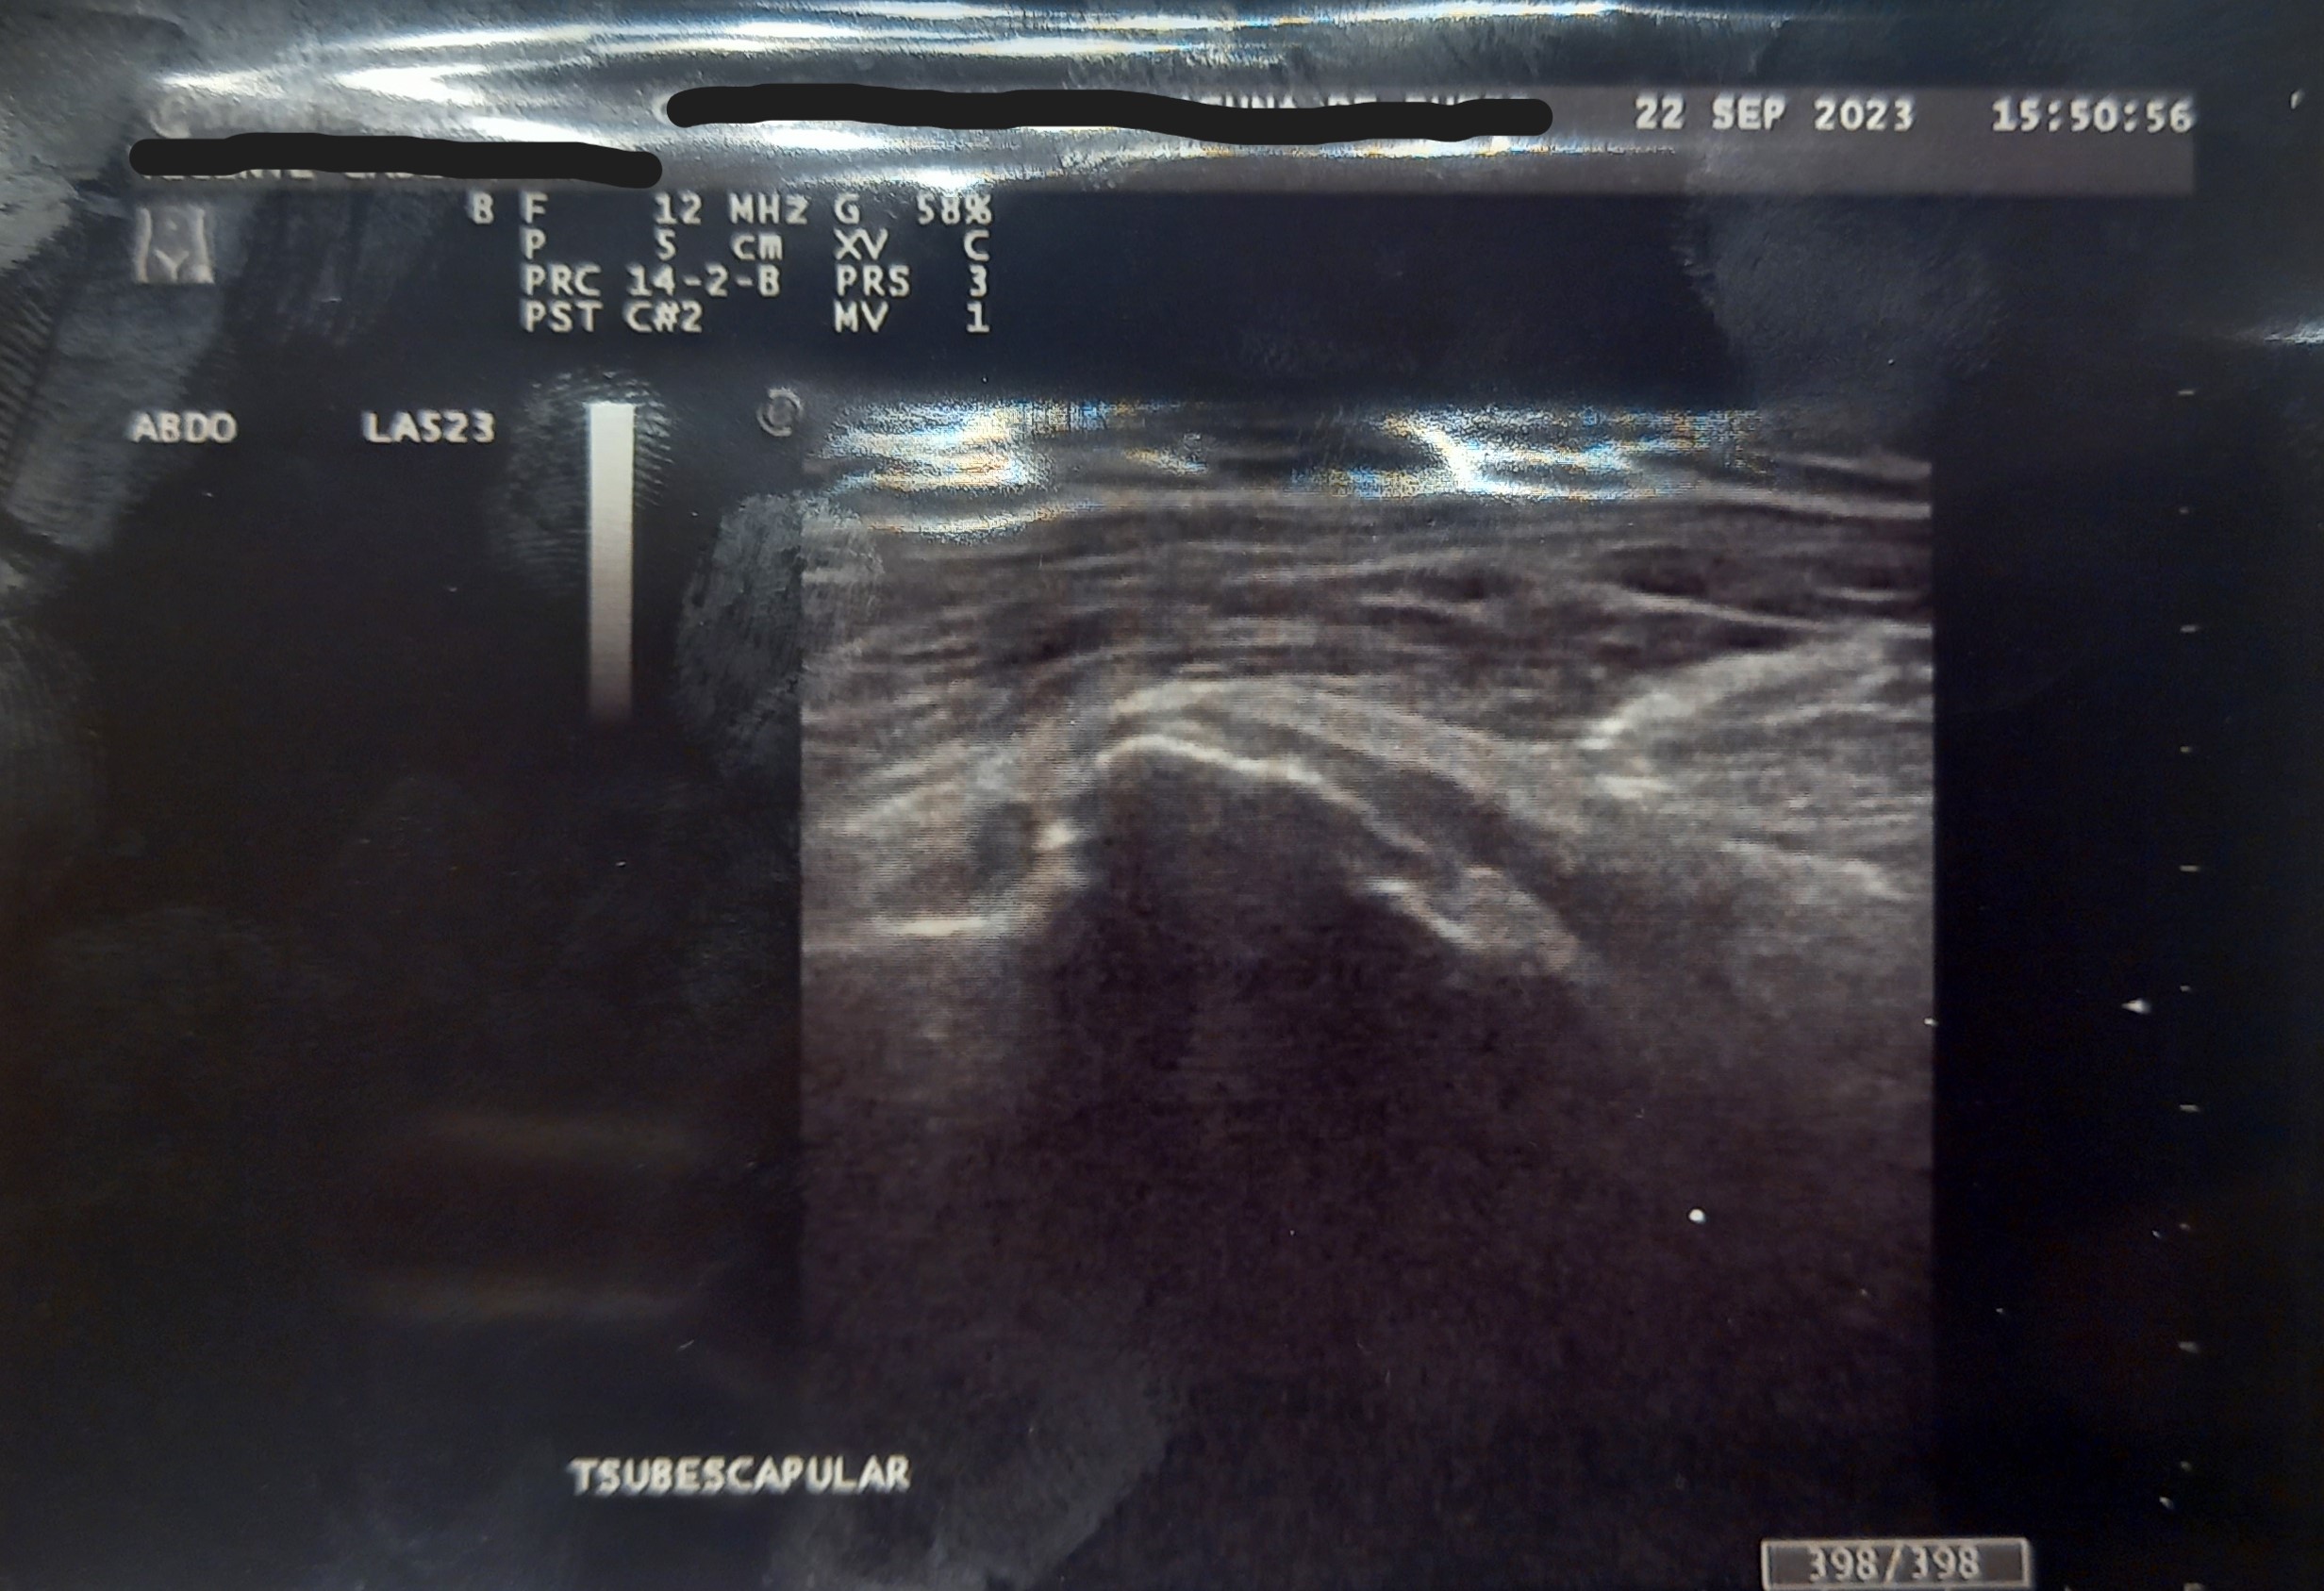

Hallazgos ecográficos

Ecografía en consulta de Atención Primaria. Se observa en la ecografía de partes blandas Patrón heterogéneo en región de tendón supraespinoso, con áreas hipo ecoicas y banda hiperecogenica compatible con tendinitis calcificante del tendón del supraespinoso. Tendón sub-escapular con áreas hipoecoicas en su trayecto que puede atribuirse a tendinosis de larga evolución.